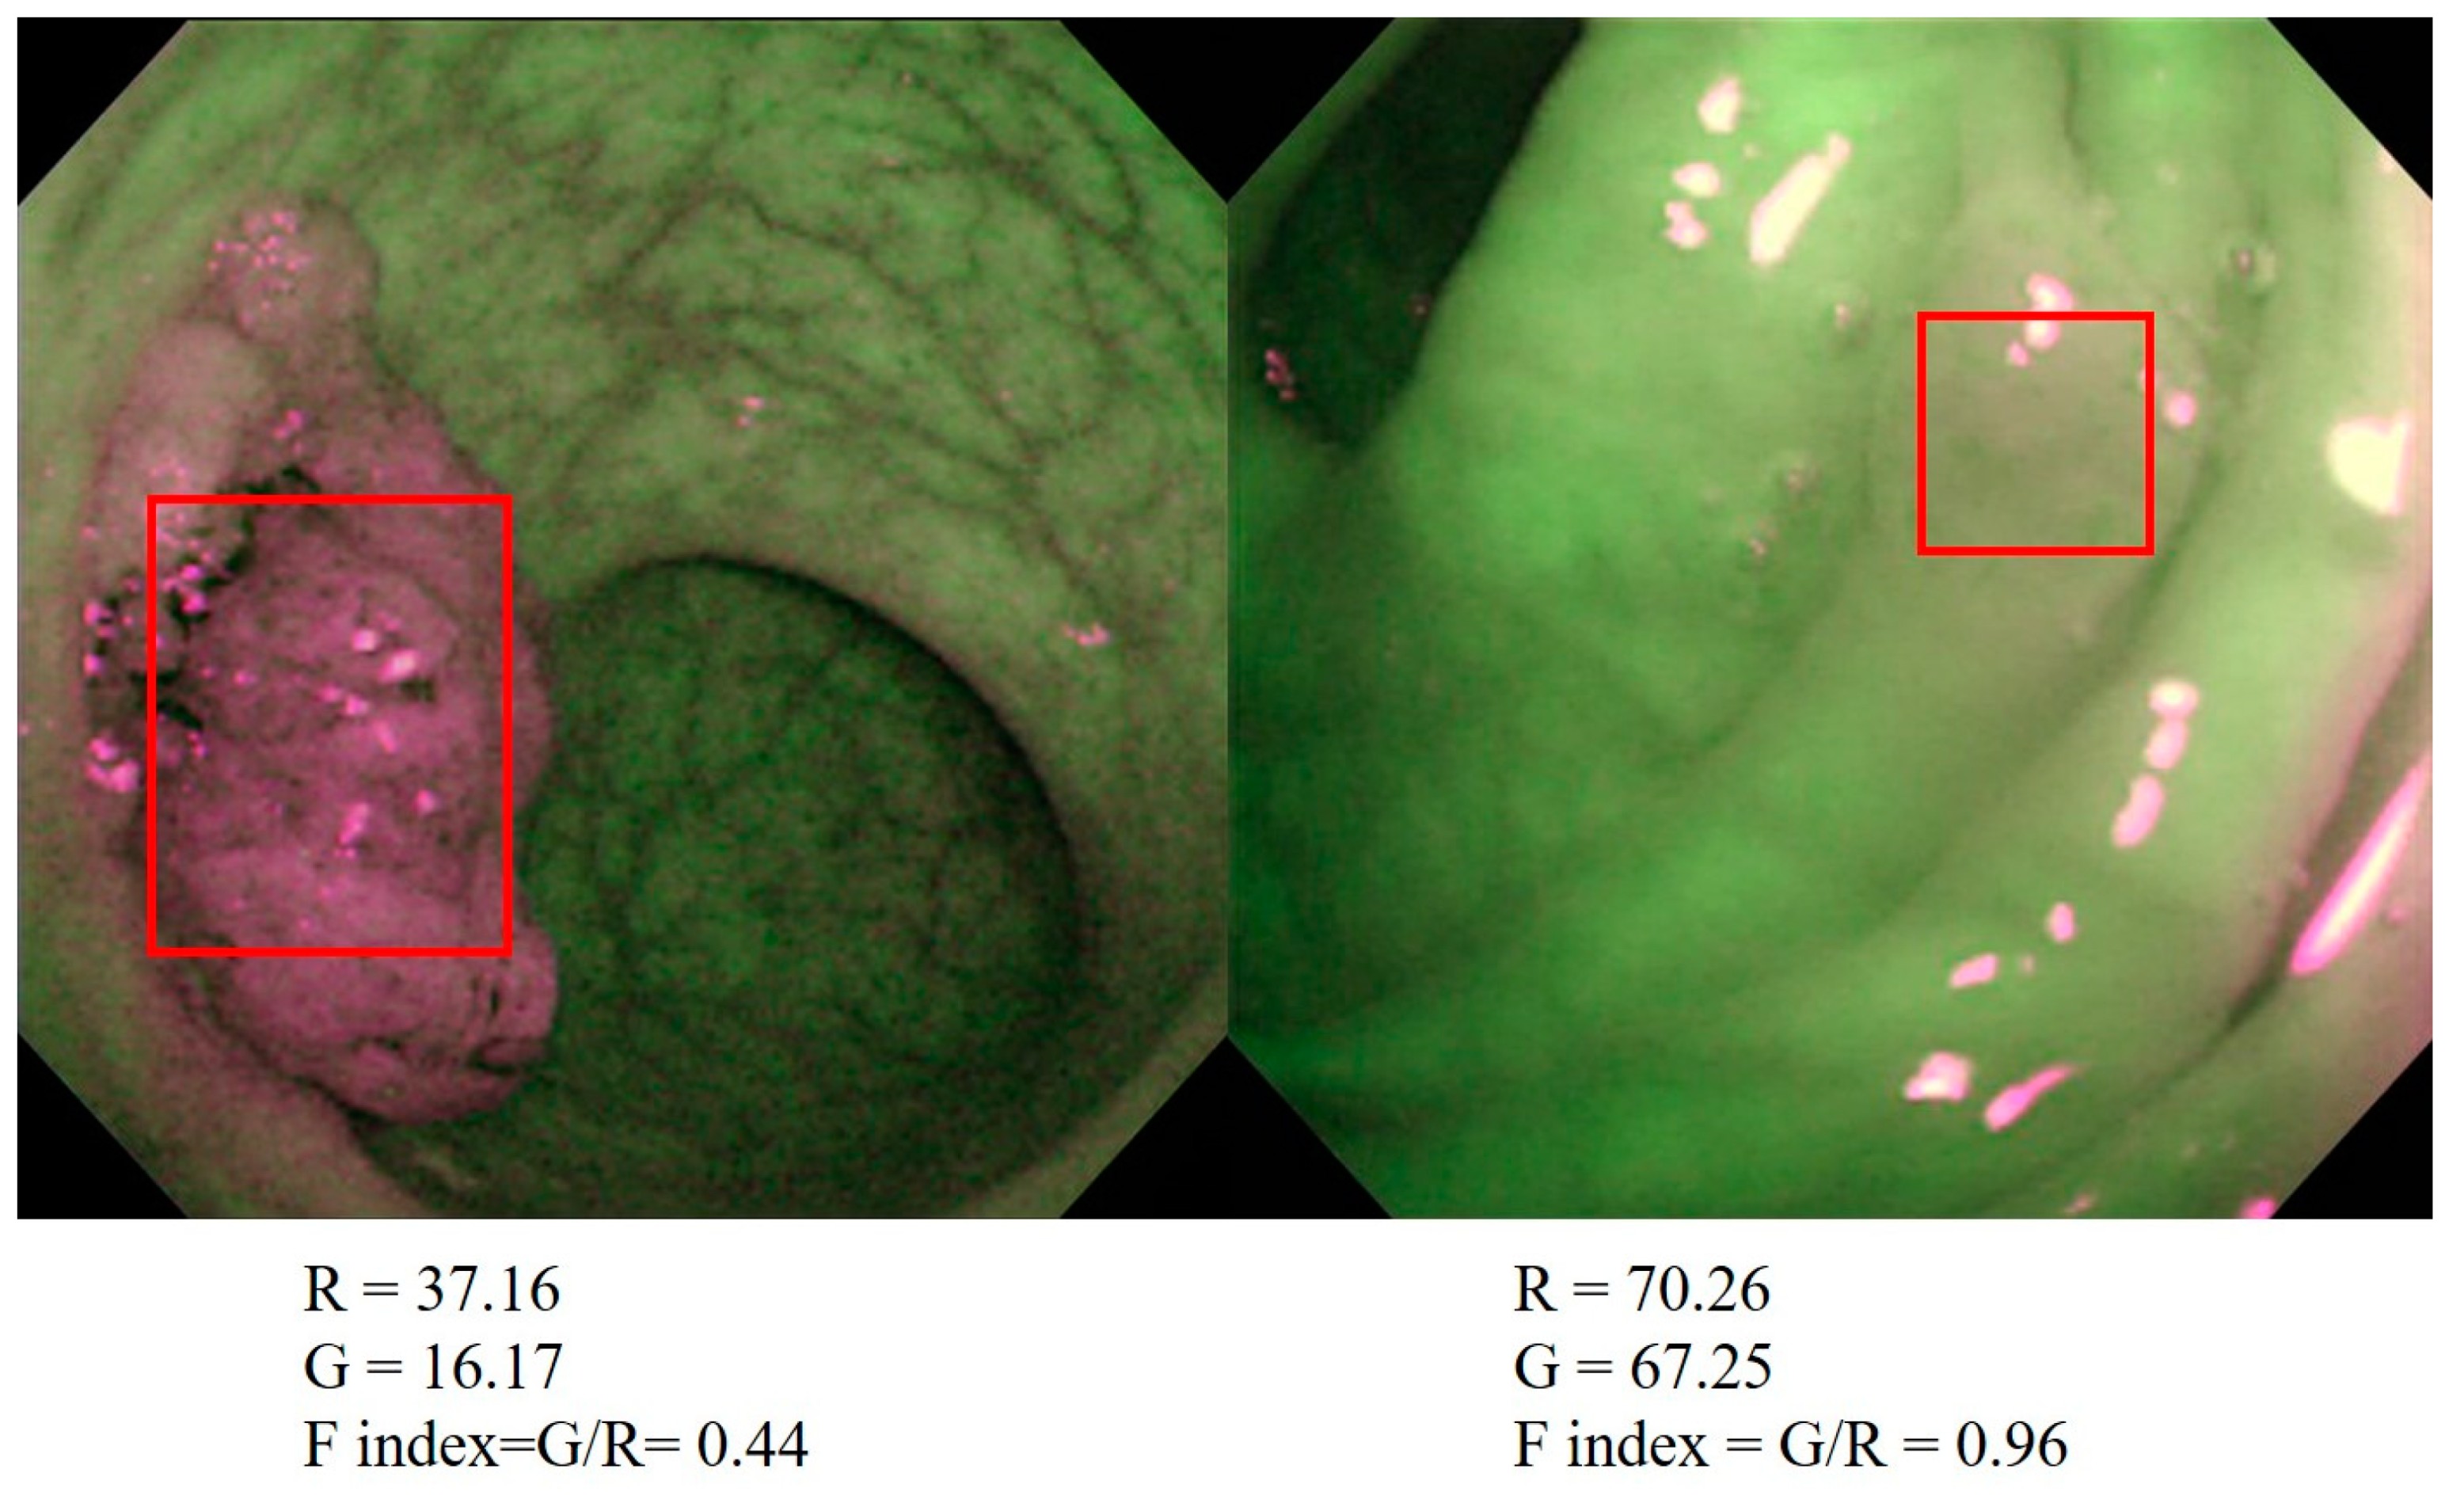

4.2. AFI